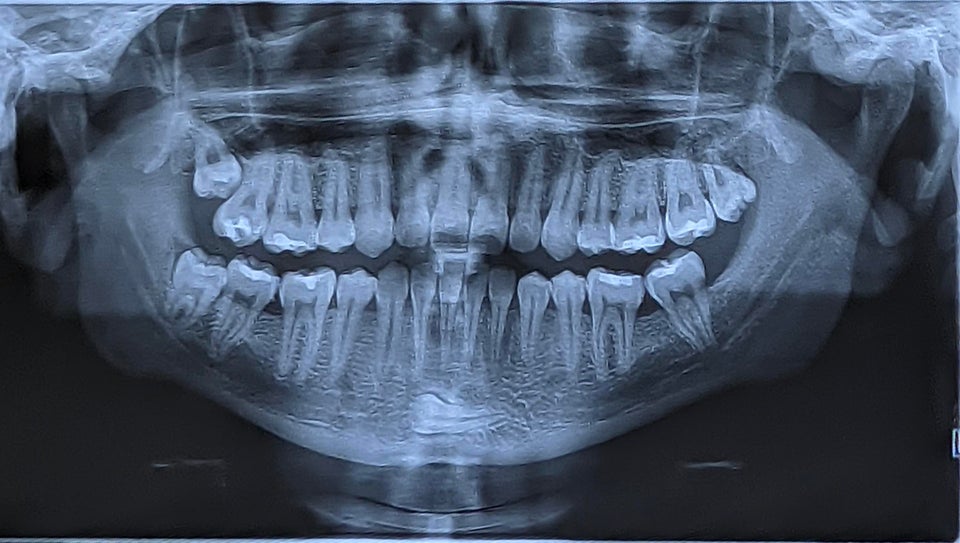

Рентген моих зубов примерно 2 месяца назад

Стоматолог был обескуражен. Сосчитаете все проколы и украшения?